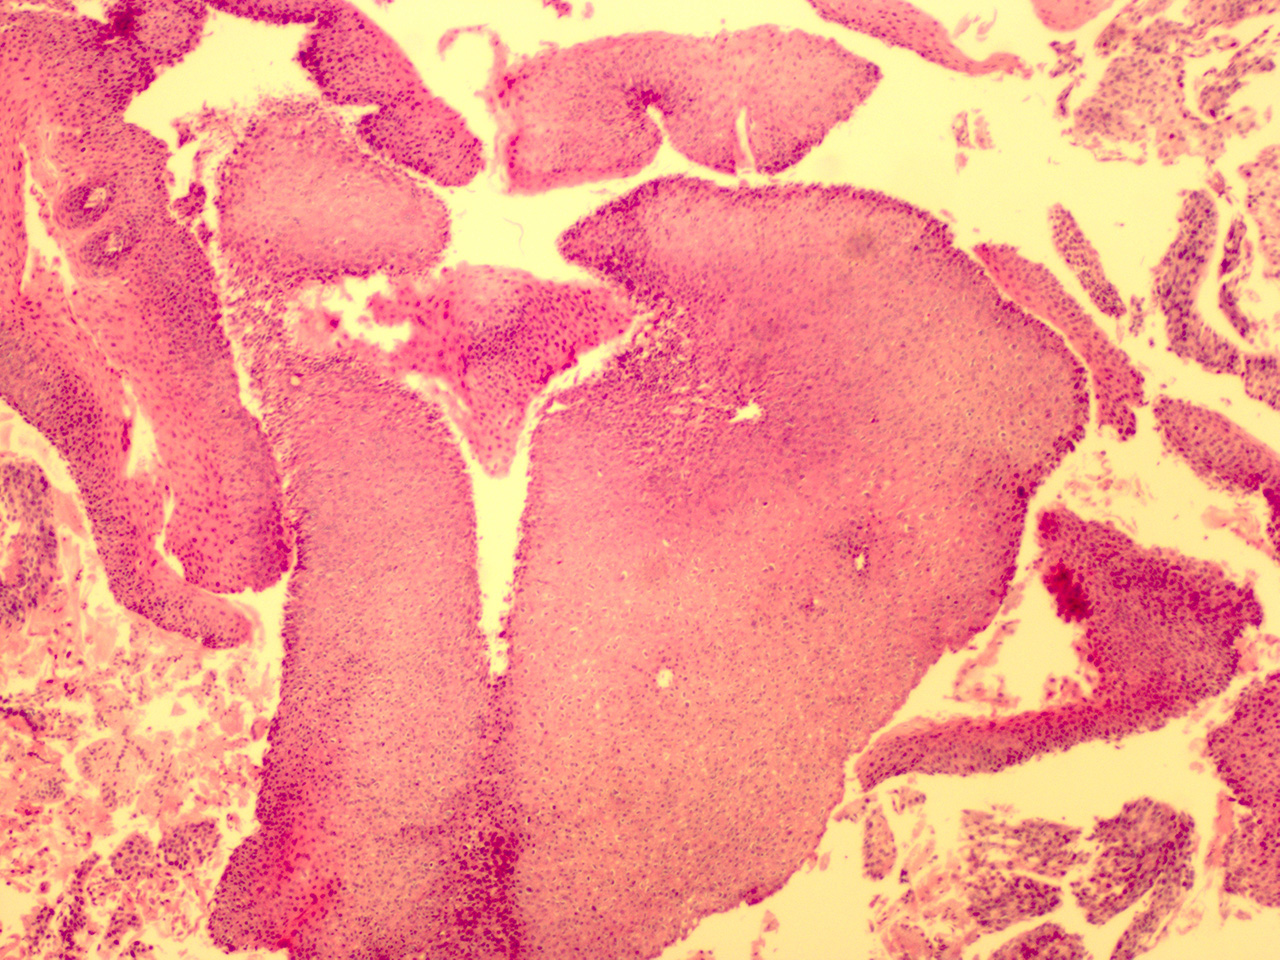

Case 2

Soft Bx  CIN 2

10x - Low Power